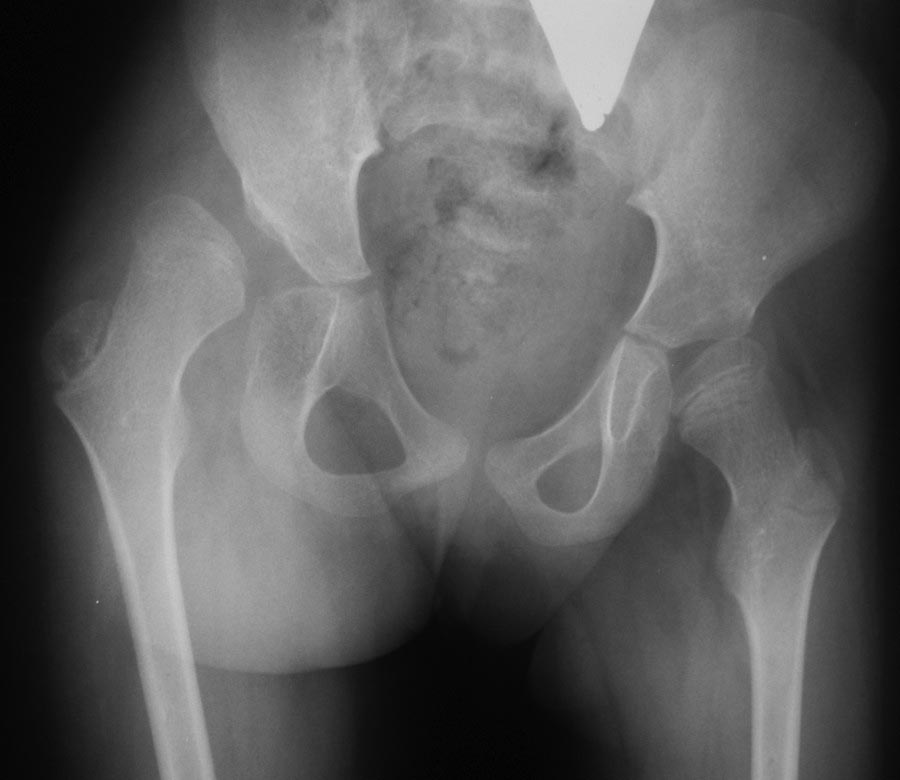

Девочка 7 лет, страдает ДЦП. Самостоятельно не ходит, практически не

стоит (стоит с поддержкой не более 1 минуты). Выраженная приводящая

контрактура.

Вопрос возник с объёмом планируемого оперативного лечения -

аддуктотомия+КОБ, либо всё-таки аддуктотомия+КОБ+Солтер? С одной

стороны, вряд ли получится достигнуть достаточно хорошего покрытия

головки без остеотомии таза. С другой стороны, учитывая длительную

гипсовую иммобилизацию после полного объёма операции, и текущий

неврологический статус, не хотелось бы, чтобы ребёнок потерял даже

имеющиеся моторные навыки. Не хотелось бы лечить рентгенограмму.